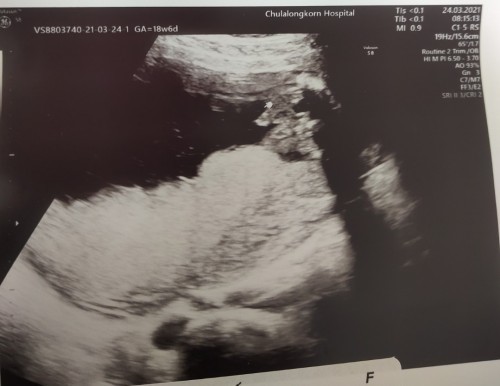

แบบนี้คือผู้หญิงหรือผู้ชาย คะ ดูผลอัลตร้าซาวด์ไม่เป็นจริงๆค่ะ